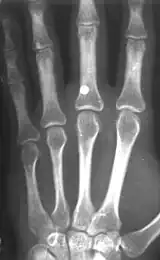

A BB with a velocity of 45 m/s (150 ft/s) has skin-piercing capability, and a velocity reaching 60 m/s (200 ft/s) can fracture bone.[7] This is potentially lethal, and this potential increases with velocity, but also rapidly decreases with distance. The effective penetrating range of a BB gun with a muzzle velocity of 120 to 180 m/s (390 to 590 ft/s) is approximately 18 m (60 ft). A person wearing jeans at this distance would not sustain serious injury. However, even at this distance a BB still might penetrate bare skin, and even if not, could leave a severe and painful bruise. The maximum range of a BB gun in the 120 to 180 m/s (390 to 590 ft/s) range is 100–200 metres approximately (https://www.earmi.it/balistica/balest.htm), provided the muzzle is elevated to the optimum angle.

- Tsui, Cl; Tsui, Kl; Tang, Yh (November 2010). "Ball Bearing (BB) Gun Injuries". Hong Kong Journal of Emergency Medicine. 17 (5): 488–491. CiteSeerX 10.1.1.1088.5686. doi:10.1177/102490791001700510. S2CID 9643574.